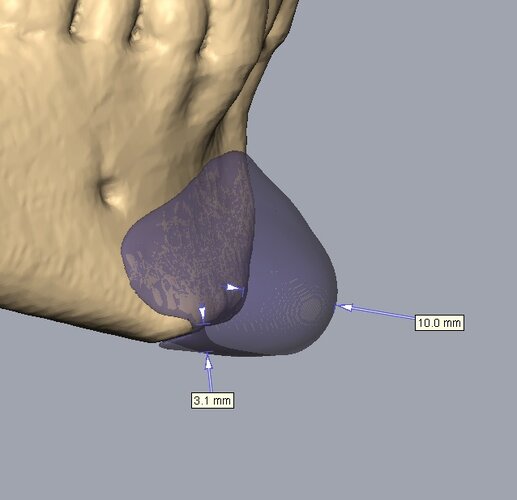

Recieved the draft 1 of the design, what changes should i ask for?? a couple of things i can think of are malar implants not giving enough lateral protrusion, gonion flaring.

I also am planning to include infra implants as well.